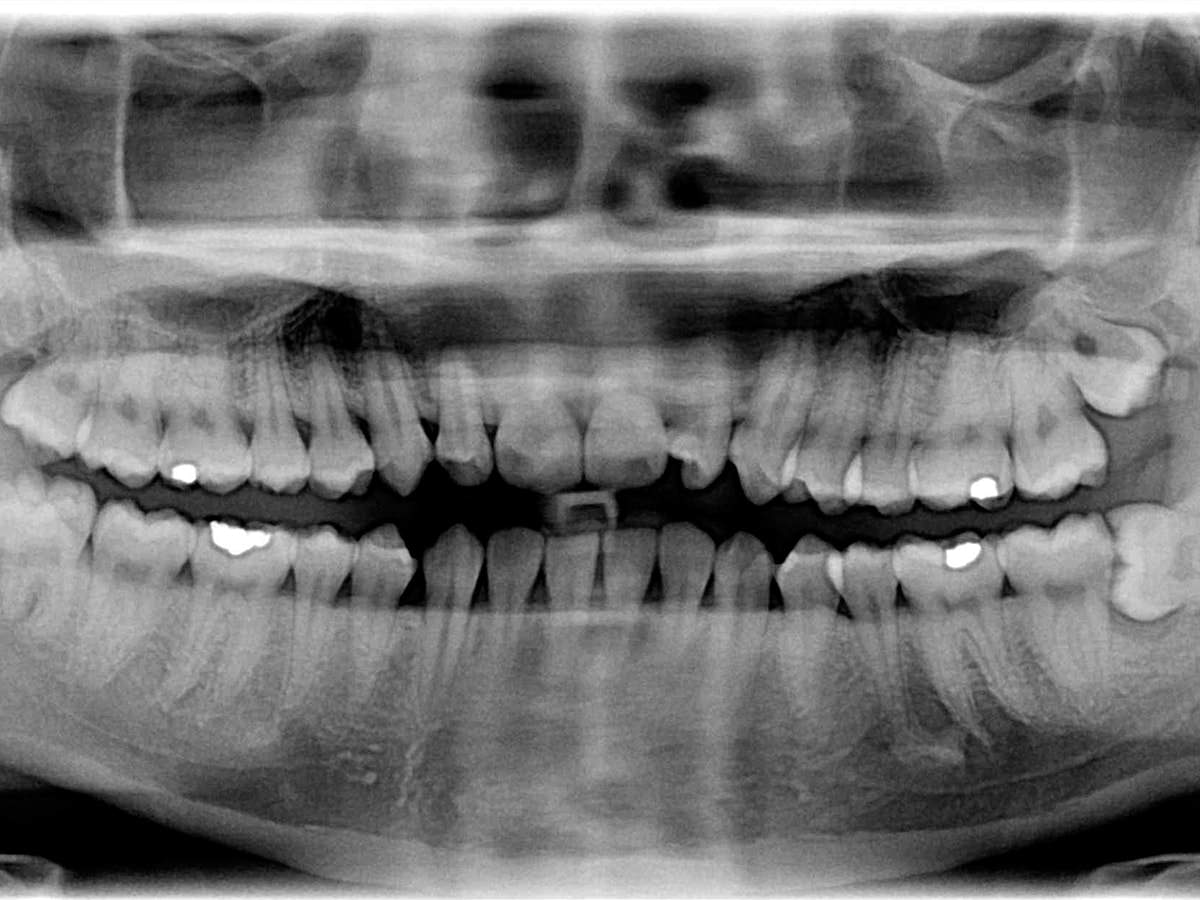

Titelbild

Foto: WikiCommons

Der Klassiker unter den Zahnfüllungen ist Amalgam. Es besteht zur Hälfte aus Quecksilber, einem giftigen Schwermetall. Ein Verbot wäre dennoch nicht sinnvoll.